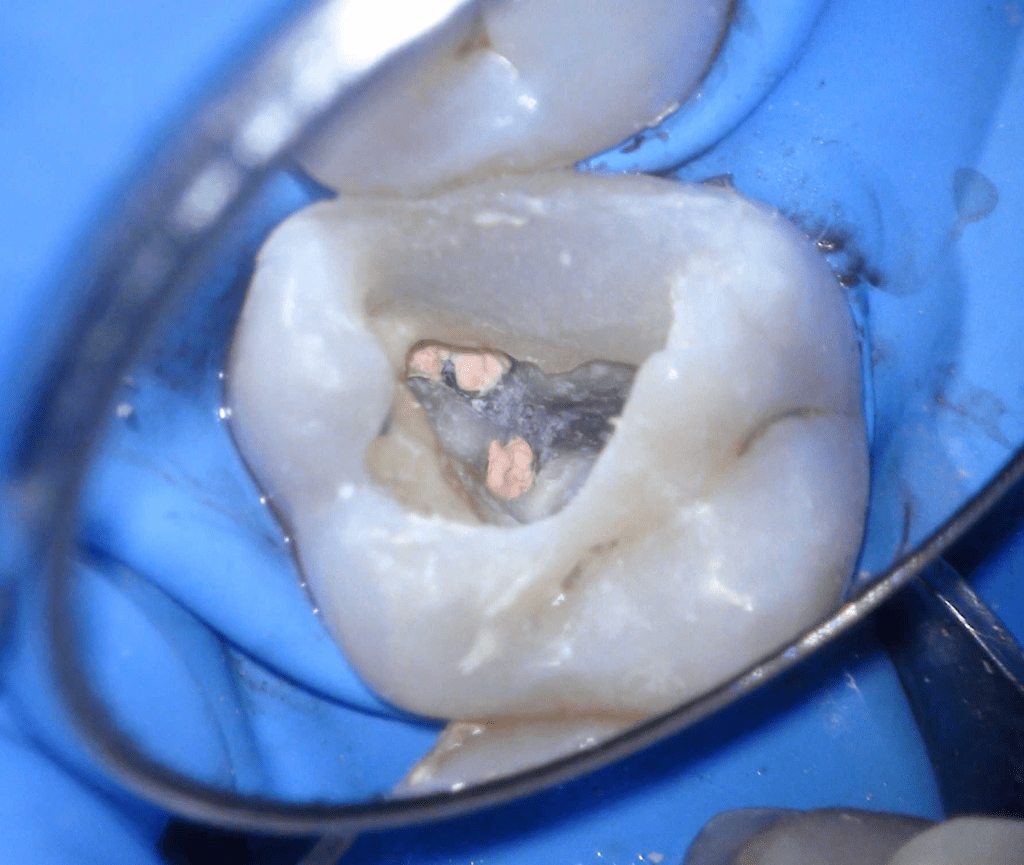

Fisura, remoción amalgama para explorar